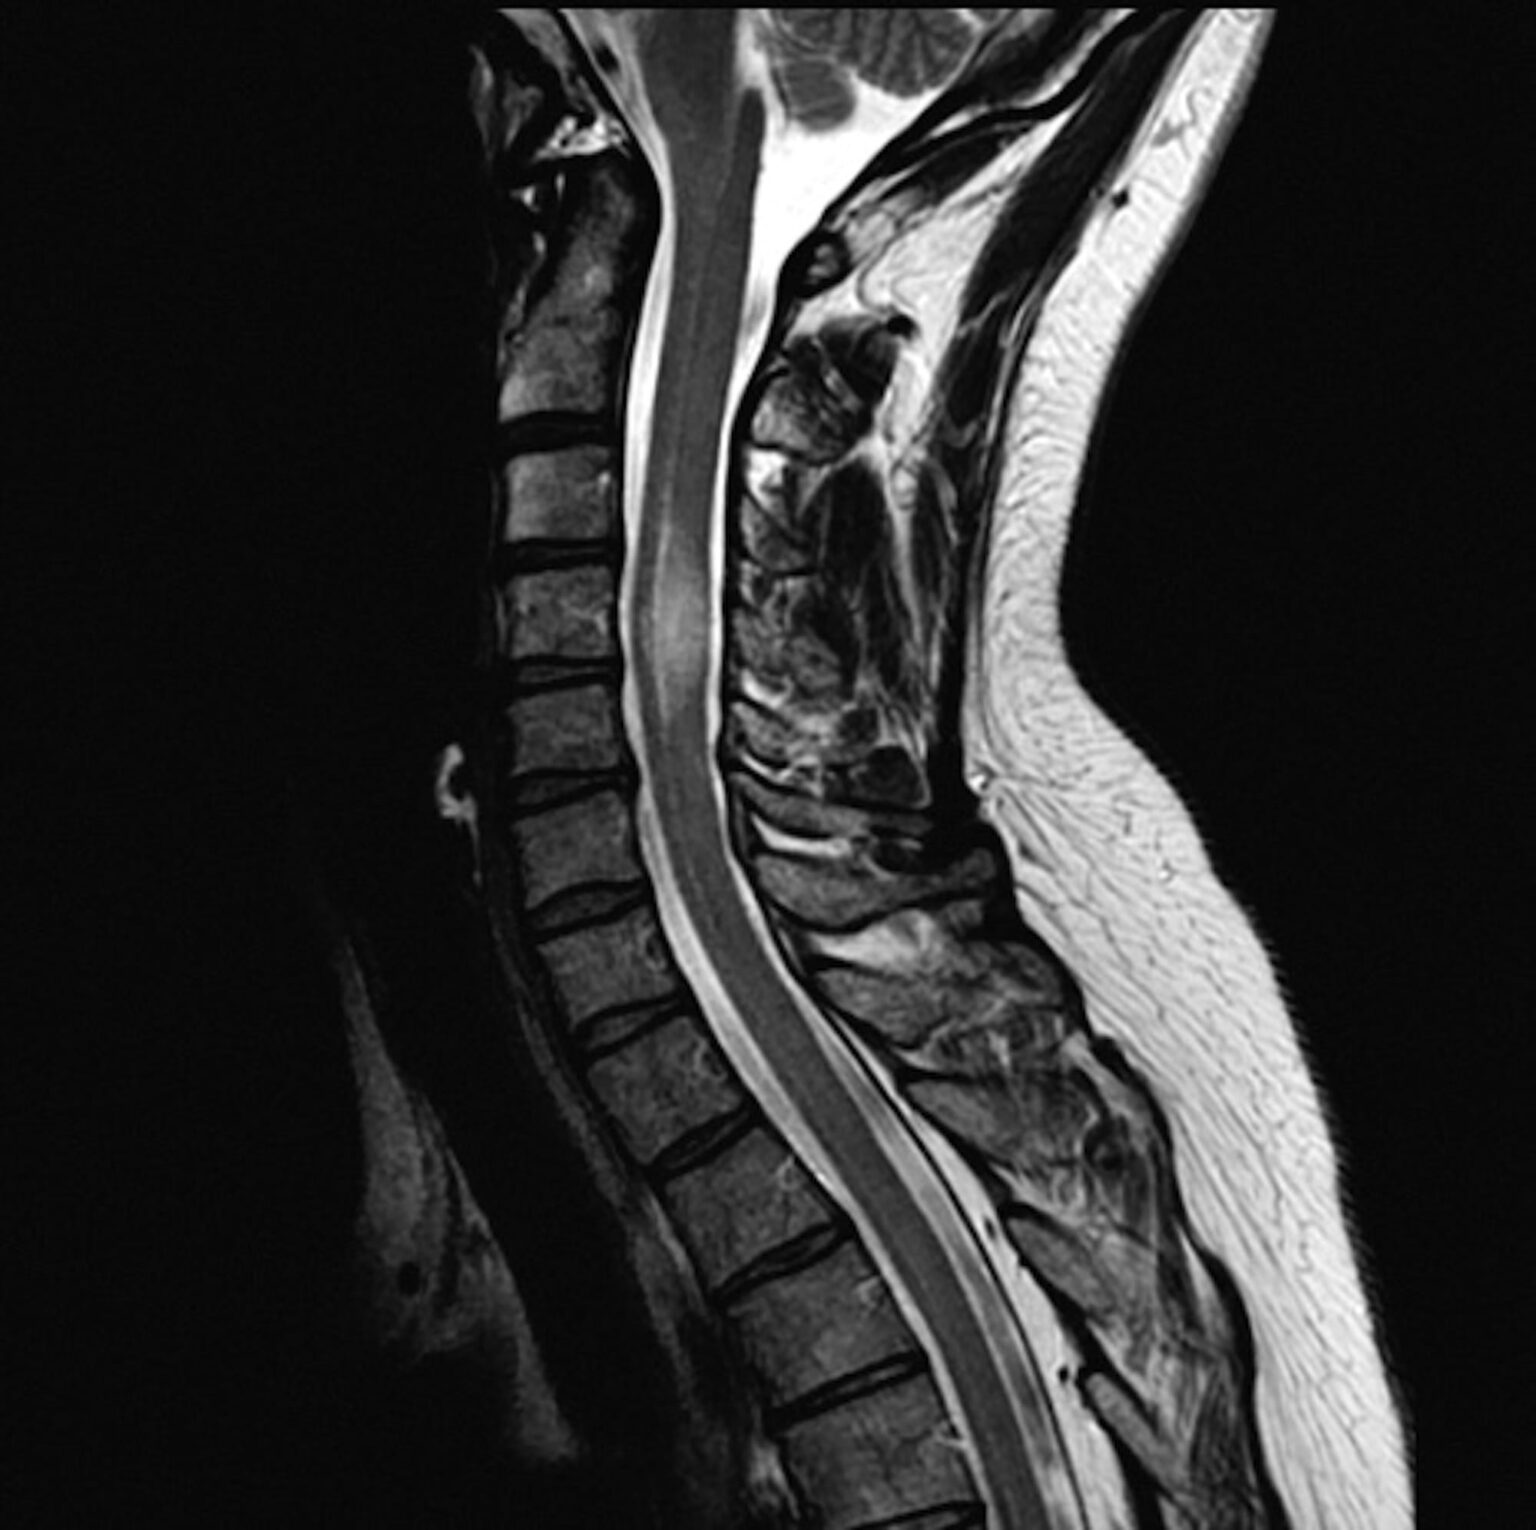

First off, what exactly is a myelogram? It's a specialized diagnostic imaging procedure used to examine the spinal canal. Doctors use it to look at the spinal cord, nerve roots, and other structures to identify problems like herniated discs, spinal stenosis, tumors, or inflammation. During the procedure, a special contrast dye is injected into the spinal fluid, making these structures visible on X-ray, CT scans, or sometimes MRI.